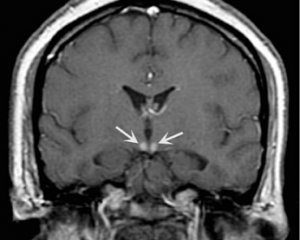

- Энцефалопатия Вернике, возникающая из-за нехватки тиамина, с поражением таламуса и среднего мозга.

Энцефалопатия Вернике

– это заболевание, которое чаще всего возникает при хроническом алкоголизме, но также может развиваться на фоне злокачественных опухолей, длительной рвоты, голодания или СПИДа. Основные симптомы включают страх и тревогу, двигательное возбуждение, галлюцинации – это предвестники делирия. Физическое истощение сопровождается повышением температуры, учащенным сердцебиением и аритмией. В течение нескольких дней состояние оглушенности может прогрессировать до ступора и комы.